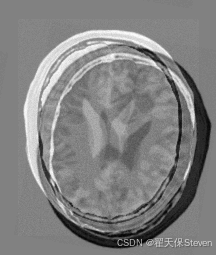

测试效果

官方给定的浮动图像在 X 轴方向偏移了 13 像素,Y 轴方向偏移了 17 像素,并旋转了10度,理想情况下配准结果应该接近这三个值。在实际运行中,优化器会找到最优的变换参数,输出类似如下的结果:

从结果可以看出,配准得到的平移量非常接近真实偏移量,说明配准算法成功地找到了最优变换参数。但也能看出仍存在一定位移偏差,官方也给出了解释,因为配准示例中采用了质心对齐的方法,而人为创造偏差时并不是这样处理的,所以整体的平移会有偏差。

过程图像如下:

配准后两图差值